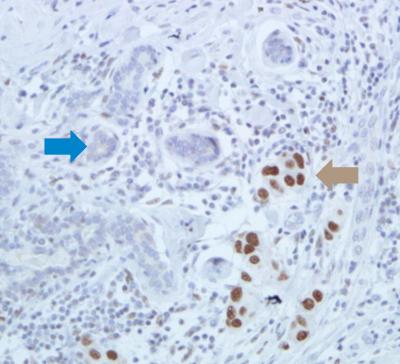

To see how HSF1 levels in cancer cell nuclei are associated with the cancer's aggressiveness, Santagata examined HSF1 levels in breast cancer tissue samples from 1,841 participants in one of the largest and longest-running epidemiological studies of women's health, the Nurses' Health Study. Santagata and colleagues at the Harvard School of Public Health and University of Miami then looked at the relationship between HSF1 status and the participants' outcomes. Compared with ER-positive breast cancer patients with low levels of HSF1, those with high levels of HSF1 had a poorer outcome, including increased mortality. He also noted that invasive ER-positive tumors with elevated HSF1 levels tended to be larger and more aggressive than those with normal HSF1 levels.